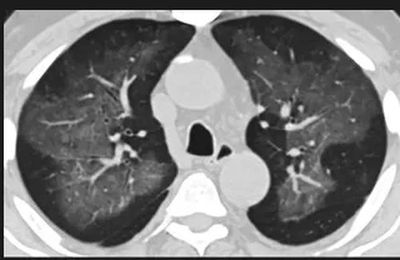

(这4张图,是专家怀疑被误诊为电子烟肺病的其中一个病例的肺片。专家表示,他们不是仅仅通过一张影片做判断的,而是通过这4张涵盖了这名病例肺部多天变化情况的影片进行的研判,认为该病例的病程进展跟新冠更为相似)